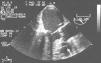

On intraoperative transesophageal echocardiography, after apical puncture, the valvuloplasty catheter impinged on the interventricular septum (Fig. 1, Video 1). When the catheter was pulled back, an iatrogenic ventricular septal defect (VSD) with a clear left-to-right shunt was detected (Fig. 2, Video 2). TA-AVI was then performed without any other complications. One year later the patient was asymptomatic and in good clinical condition. The VSD was confirmed by transthoracic echocardiography (Fig. 3, Video 3), with a Qp/Qs of 1.2.